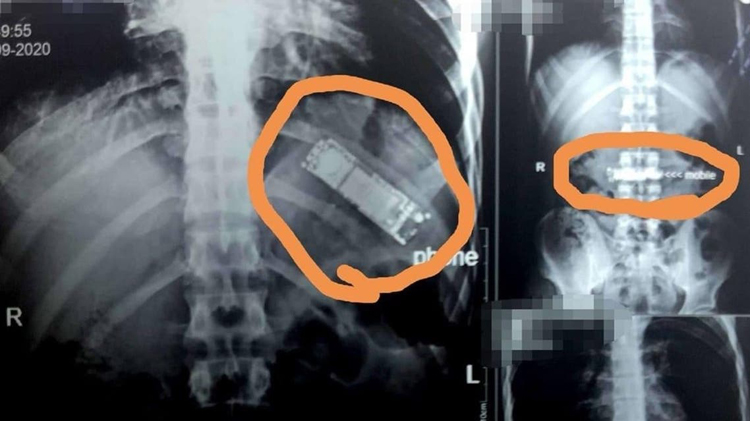

مصری مریض کے پیٹ سے سات ماہ بعد موبائل برآمد

مریض کا خیال تھا کہ قے آنے سے موبائل فون واپس باہر نکل آئے گا۔(فوٹو الوطن)

یہ شخص سینے اور پیٹ میں شدید تکلیف کی شکایت لے کر ہسپتال آیا تو اس کا مکمل چیک اپ کیا گیا۔ ایکسرے کرنے کے بعد موبائل فون کی موجودگی کا پتہ چلا۔

دریافت کرنے پر مریض نے بتایا کہ اس نے سات مہینے قبل دوستوں کےکہنے پر یہ موبائل نگل لیا تھا۔ اس کا خیال تھا کہ قے آنے سے موبائل فون واپس باہر نکل آئے گا مگر ایسا نہیں ہوا اور اس نے اہل خانہ سے اس کا ذکر بھی نہیں کیا۔

ہسپتال میں ڈاکٹروں کی ٹیم نے دو گھنٹے طویل اور کامیاب آپریشن کر کے موبائل نکال لیا ہے۔

ڈاکٹر کا کہنا ہے کہ مریض کی قسمت اچھی ہے کہ موبائل کی بیٹری پیٹ میں تحلیل نہیں ہوئی ورنہ بیٹری کے اندر موجود کاربن کے زہرآلود ہونے کے باعث اس کی جان کو خطرہ لاحق ہو سکتا تھا۔